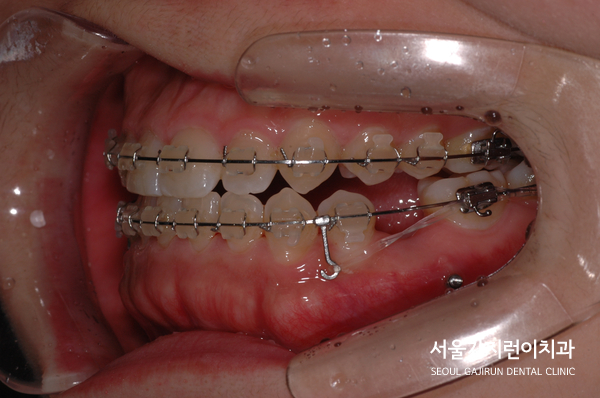

상기 환자의 경우 치아가 거꾸로 물리는 반대교합 증상을 가진 상태로 주걱턱 양상을 보이고 있었는데요.

상악앞니 절반이 가려져 있는 케이스로 아래턱이 윗턱보다 전방에 위치해 있는 것을 육안으로도 확인할 수 있었습니다.

환자분의 경우 저희 서울가지런이치과 교정과 치과 의원에서 발치를 동반한 공간 확보와 미니스크류 장치를 이용해 치아의 쓰러짐 없이 치아교정을 완성했는데요. 교정을 할 때 앞니의 경사를 조절하면서 입술의 돌출감을 개선했고 치아의 정상적인 교합을 위해 치아교정 플랜을 수립했습니다.